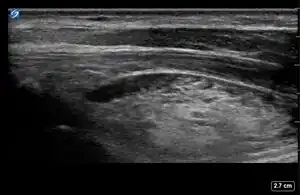

This module allows traditional bone setters, pre-hospital providers, clinical officers, nurses, nurse practitioners, and medical officers to become confident and competent in performing point-of-care ultrasound diagnostic imaging to rule out the presence of a pediatric distal forearm fracture and distinguish between buckle (torus) fractures and cortical break fractures to make appropriate referrals as part of the management of closed pediatric (< 16 years of age) distal forearm fractures in regions without access to X-ray imaging and orthopedic specialist coverage.[1][2][3][4][5][6][7][8][9]

Review all the acquired images to determine if they meet all the quality standards outlined in the checklist below.

| # | Proper Technique for Image Acquisition and Interpretation | Ultrasound Image Meets Standard | Ultrasound Image Does Not Meet Standard |